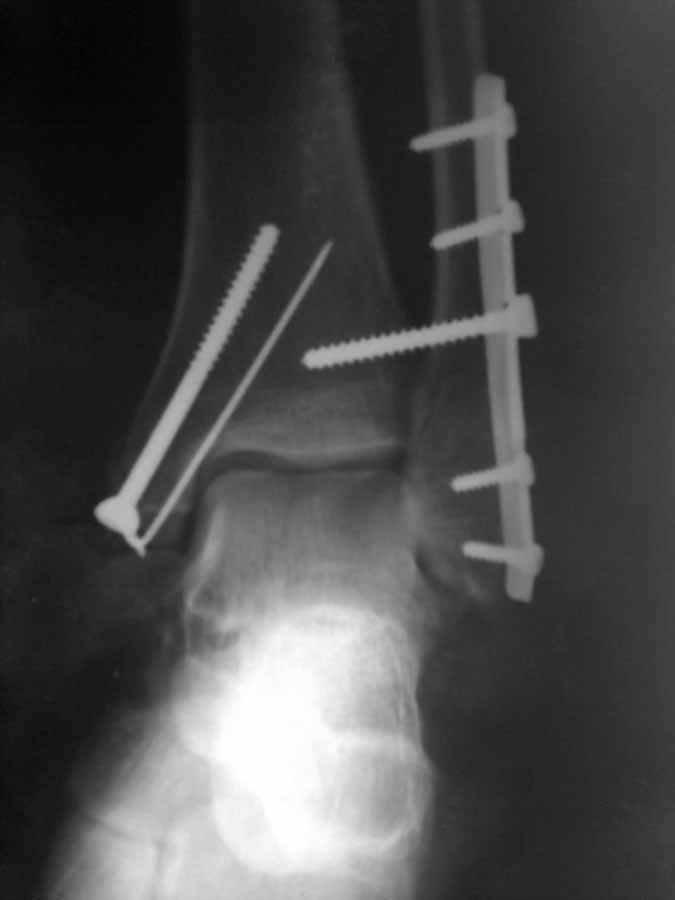

После операции высказали ряд замечаний. Не то что бы имею грандиозный опыт, но результат

считаю достаточно удовлетворительным по крайней мере для того, что бы делать реМОС (так

решило начальство. Оцените обьективно ситуацию и проясните мне - это результат моей

оплошности или предвзятое отношение